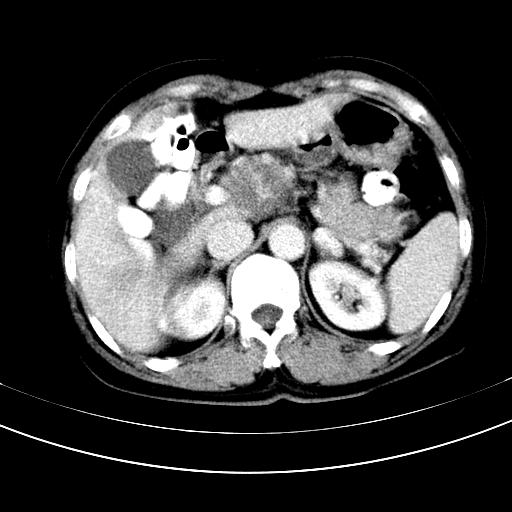

补充强化片

肝左叶及尾叶低密度灶,增强有渐进性明显强化,考虑血管瘤。胃内“充缺”首先要排除异物(食物),变换体位可鉴别。增强时机抓的不好,还应该有延时像。

谢谢楼主的增强片子,平扫没发现左侧肾上腺的问题很不好意思,可惜片子只有门脉期,所以还只有猜,肝脏的病灶在门脉期部分强化,首先考虑为血管瘤(其他的用一种病不好解释)胃要喝水就好了现在不好说是否有问题,左肾上腺的问题考虑是肿瘤。

做了增强后,可以明确胃是没有肿瘤的,肾上腺也没有肿瘤.肝左叶的病灶首先考虑血管瘤,应该再延迟,肝尾状叶的病灶仍不能排除肝癌的可能性.